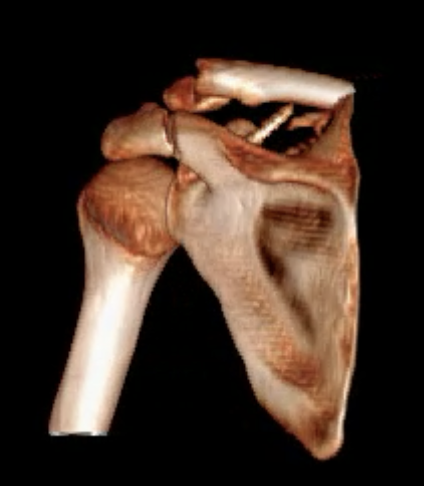

Glenoid fracture + lateral clavicle fracture + acromial fracture